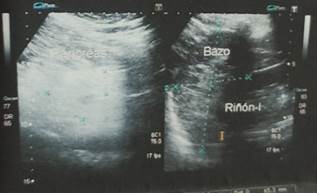

Se realizó exámenes de imagen en donde en la ecografía de abdomen superior se reporta: hígado aumento de ecogenicidad en relación a esteatosis hepática leve, bazo de tamaño y aspecto normal

Figura 3. Ecografía abdominal: hígado aumento de ecogenicidad.

Figura 4. Ecografía abdominal: bazo de tamaño y aspecto normal.